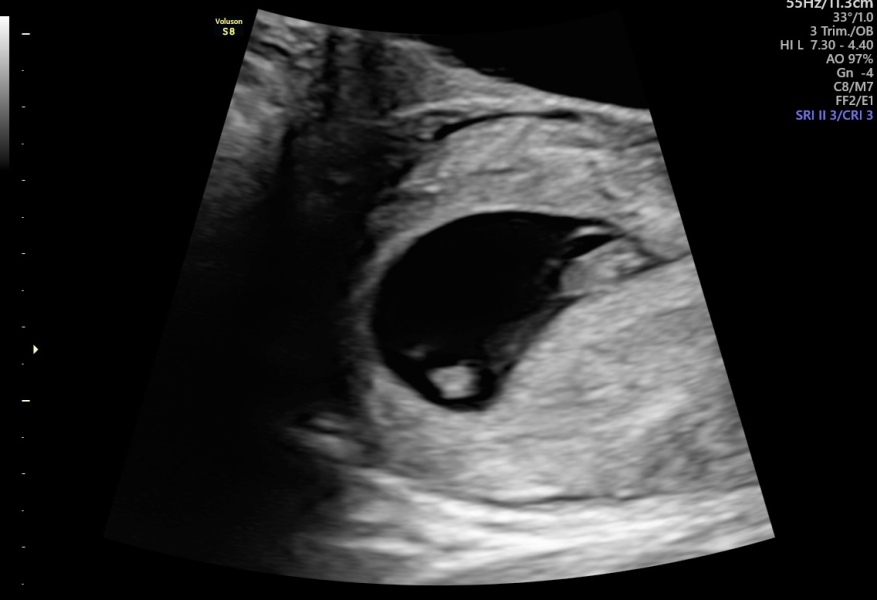

I work in obstetric sonography OP. The consultant is talking bollocks I'm afraid. At 5 weeks it's far far to early to see much of anything. 'Busy and full' is not a medical diagnosis and she was wrong to tell you these things. What was this consultants speciality?

From your pictures, it does look like a single embryonic sack, yolk sac and fetal pole, in the second image. Neither image indicates twins in anyway. By 6 weeks you'd expect some definition between the two embryos if everything is developing correctly. Your sonographer should have checked the whole sac very thoroughly, and if there was more than one heartbeat, usually they will have picked that up at the same time.

Second one looks like my 7 week singleton pregnancy scans x

yours to the very much untrained eye looks like a singleton to me. I’ll be honest an ID twin pregnancy comes with complications, we’ve been okay and majority are but there are risks associated which wouldn’t be the case with a singleton!